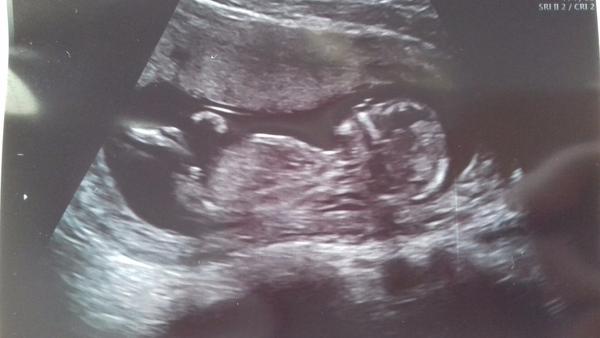

Ano, já jsem právě myslela podle toho výběžku, já jsem na to slepoň, tak jsem se přišla zeptat, co kdo vidí 😊

Tak jo, takže opravdu kluk 😂